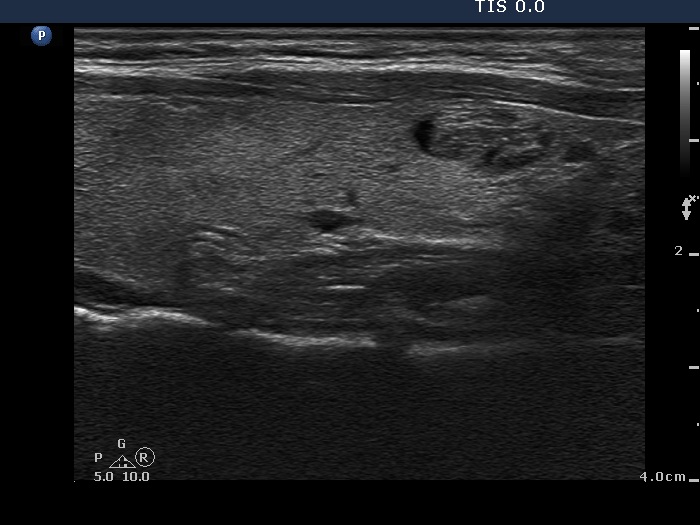

Comments:

The ultrasound pattern of de Quervain's thyroiditis and that of papillary cancer are very similar: a hypoechogenic lesion with blurred borders are found in both cases. They differ in vascularization statistically but the vascular pattern has only limited practical significance. In the acute phase of de Quervain's thyroiditis the vascularization is generally decreased but even in this case the situation was the opposite. The finding of not one but multiple hypoechogenic areas favored the possibility of subacute thyroiditis.

We did not administer anti-inflammatory drugs because the patient was pregnant. Therefore, the hypoechogenic areas of the left thyroid decreased very slowly.

The relapse of de Quervain's thyroiditis in the contralateral lobe is a very frequent finding but not one year after the appearance of the disease. We supposed that the immunological changes during and after pregnancy explained the relatively late relapse of the disease.